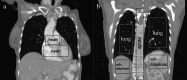

Methods: With the dual-view DTS technique, limited angle scans are performed and projection images are acquired in two orthogonal views: PA and lateral. The dual-view projection data are used together to reconstruct 3D images using the maximum likelihood expectation maximization iterative algorithm. In this study, projection images were simulated or experimentally acquired over 360° using the scanning geometry for cone beam computed tomography (CBCT). While all projections were used to reconstruct CBCT images, selected projections were extracted and used to reconstruct single- and dual-view DTS images for comparison with the CBCT images. For realistic demonstration and comparison, a digital chest phantom derived from clinical CT images was used for the simulation study. An anthropomorphic chest phantom was imaged for the experimental study. The resultant dual-view DTS images were visually compared with the single-view DTS images and CBCT images for the presence of image artifacts and accuracy of CT numbers and anatomy and quantitatively compared with root-mean-square-deviation (RMSD) values computed using the digital chest phantom or the CBCT images as the reference in the simulation and experimental study, respectively. High-contrast wires with vertical, oblique, and horizontal orientations in a PA view plane were also imaged to investigate the spatial resolutions and how the wire signals spread in the PA view and lateral view slice images.

Results: Both the digital phantom images (simulated) and the anthropomorphic phantom images (experimentally generated) demonstrated that the dual-view DTS technique resulted in improved spatial resolution in the depth (PA) direction, more accurate representation of the anatomy, and significantly reduced artifacts. The RMSD values corroborate well with visual observations with substantially lower RMSD values measured for the dual-view DTS images as compared to those measured for the single-view DTS images. The imaging experiment with the high-contrast wires shows that while the vertical and oblique wires could be resolved in the lateral view in both single- and dual-view DTS images, the horizontal wire could only be resolved in the dual-view DTS images. This indicates that with single-view DTS, the wire signals spread liberally to off-fulcrum planes and generated wire shadow there.